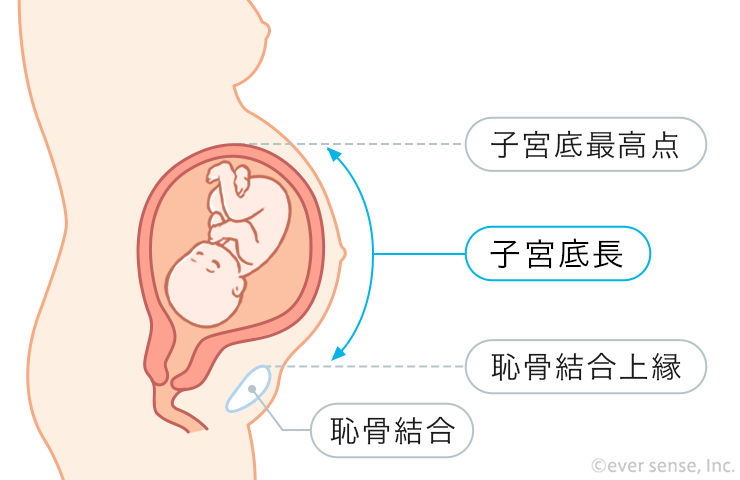

医師監修 妊娠16週 妊娠5ヶ月:妊娠中期 ゼクシィBaby。

妊娠16週から始まる妊娠5ヶ月目の胎児と母体の状態 16週、17週、18週、19週 -おむつのムーニー 公式 ユニ・チャーム。

妊娠から出産までに母胎に起こる変化 妊娠中期ホームメイト。